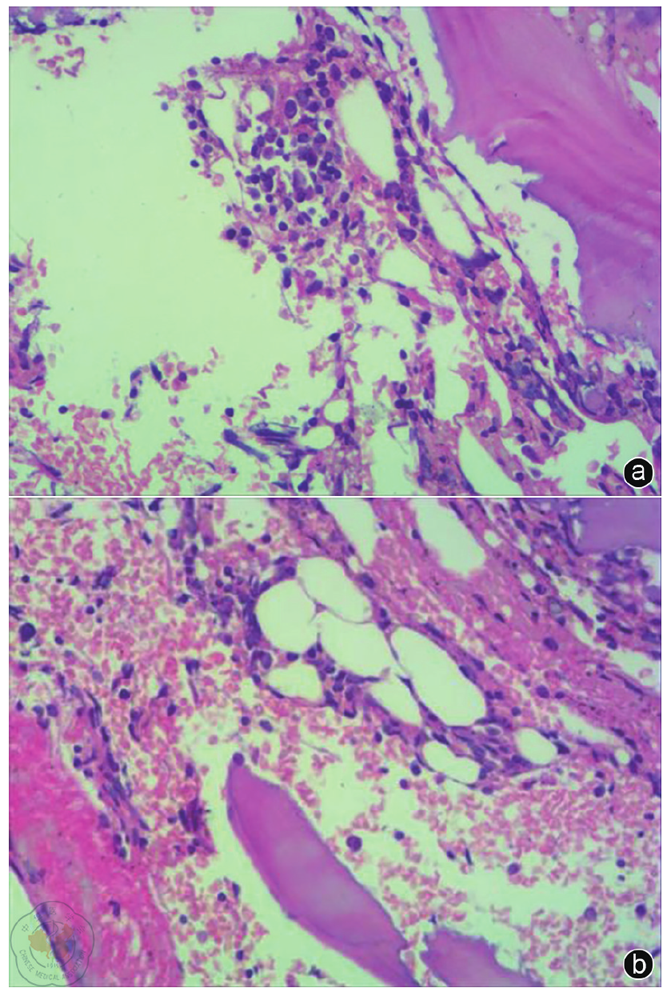

图1 毒性弥漫性甲状腺肿合并桥本甲状腺炎患者甲状腺超声图像注:a图示甲状腺实质回声弥漫性增粗减低;b图示甲状腺内部血流信号稍丰富(箭头所示)

患者33岁,初诊时甲状腺功能显著亢进,游离三碘甲状腺原氨酸(16.23 pmol/L)、游离甲状腺素(45.38 pmol/L)水平升高,促甲状腺激素水平低下(0.006 U/L),促甲状腺激素受体抗体及甲状腺过氧化物酶抗体阳性,甲状腺摄碘率增高(2 h 49.40%,6 h 80.90%,24 h 94.10%)。超声提示甲状腺轻度肿大、实质回声弥漫性减低不均且血流稍丰富,符合GD病合并桥本甲状腺炎表现,且伴粒细胞减少。予以甲巯咪唑治疗后,患者出现骨髓抑制(表现为粒细胞缺乏、红细胞及血小板减少),继发急性化脓性扁桃体炎,并诱发甲亢危象(BWPS评分45分)。骨髓活检提示造血组织增生低下,关键免疫学检查发现抗核抗体(≥1∶160)及抗Sm抗体阳性,考虑DILE所致血液系统损害。停用甲巯咪唑,经积极抗感染,应用重组人粒细胞刺激因子、糖皮质激素、免疫抑制剂及后续碘-131治疗后,患者感染控制,血常规逐渐恢复正常。甲状腺功能于碘-131治疗后转为亚临床甲减,补充左甲状腺素钠片后恢复正常。患者DILE相关指标(抗核抗体滴度)下降,糖皮质激素及免疫抑制剂用量减少,病情稳定。

The patient, a 33-year-old woman, presented with significant hyperthyroidism at initial diagnosis, characterized by elevated levels of free triiodothyronine (FT3) (16.23 pmol/L) and free thyroxine (FT4) (45.38 pmol/L), decreased thyroid-stimulating hormone (TSH) levels (0.006 U/L), positive thyrotropin receptor antibody (TRAb) and thyroid peroxidase antibody (TPOAb), and increased thyroid iodine uptake (2 h 49.40%, 6 h 80.90%, 24 h 94.10%). Ultrasonography revealed a mildly enlarged thyroid with diffuse heterogeneous hypoechogenicity and slightly increased vascularity, consistent with the clinical presentation of GD complicated by HT, accompanied by granulocytopenia. Methimazole therapy induced myelosuppression (characterized by agranulocytosis, anemia, and thrombocytopenia), leading to secondary acute suppurative tonsillitis and triggering a thyroid storm (BWPS score 45). A bone marrow biopsy revealed hypoplasia of hematopoietic tissue. Key immunological tests were positive for antinuclear antibodies (≥1∶160) and anti-Sm antibodies, suggesting hematologic damage caused by DILE. After discontinuation of methimazole, aggressive antimicrobial therapy, administration of recombinant human granulocyte colony-stimulating factor (G-CSF), glucocorticoids, immunosuppressants, and subsequent I131 therapy, the patient′s infection was controlled. Complete blood count parameters gradually normalized. Thyroid function converted to subclinical hypothyroidism after I131 therapy and normalized with levothyroxine supplementation. DILE-related markers (antinuclear antibody titers) decreased, allowing for a reduction in glucocorticoid and immunosuppressive doses, and the patient′s condition remained stable.